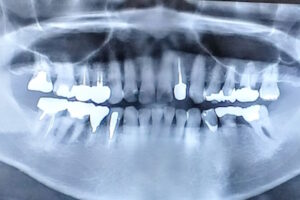

27397372_s – 64